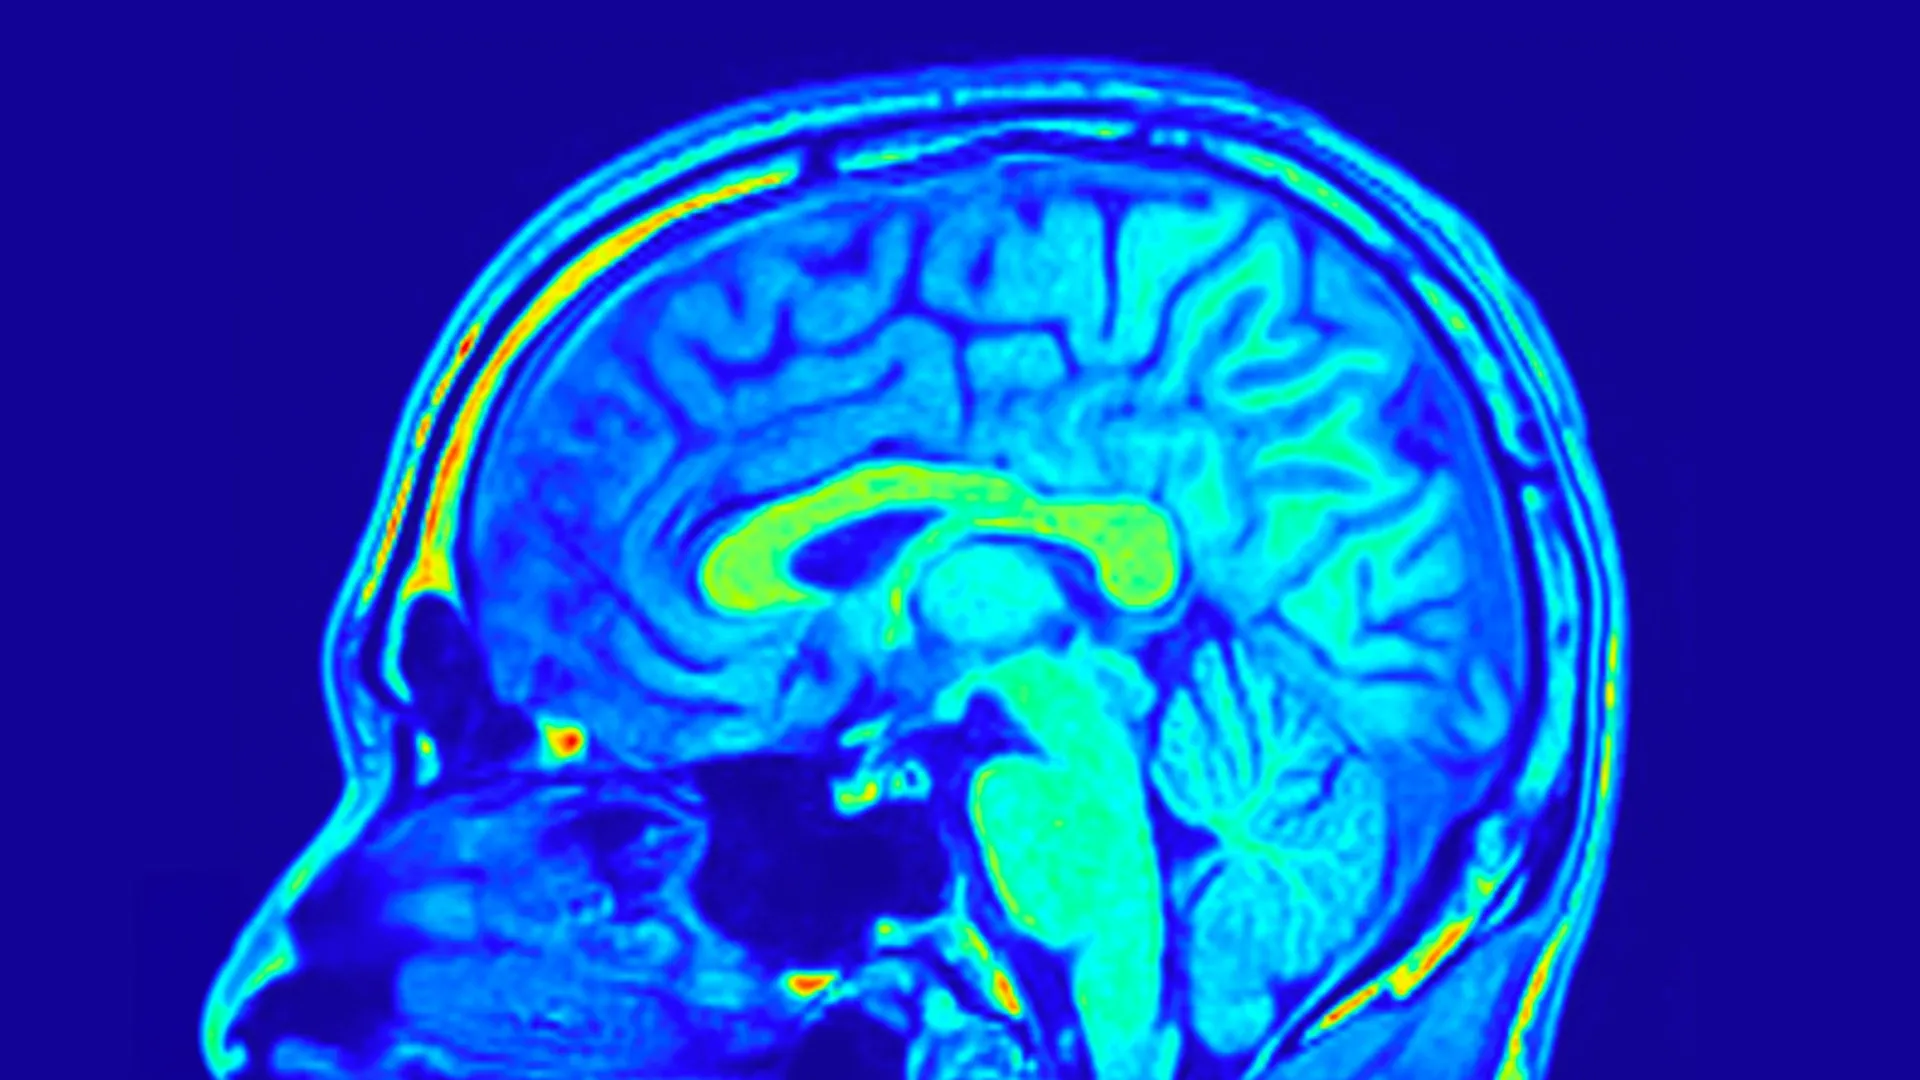

تعتبر فحوصات الدماغ خطوة جديدة في علاج الاكتئاب، حيث تقدم رؤى علمية قد تغير طريقة معالجة هذه الحالة.

أحد أسباب هذا التحدي هو الافتقار إلى أدوات واضحة وموضوعية يمكنها مساعدة الأطباء على التنبؤ بالعلاج الأفضل لشخص معين. لا تزال معظم قرارات العلاج تعتمد على الأعراض والتاريخ الطبي والخبرة بدلاً من العلامات البيولوجية. دراسة حديثة نشرت في الطب النفسي العام انطلقت لاستكشاف ما إذا كان الطب الصيني التقليدي (TCM) يمكن أن يقدم رؤى جديدة في علاج MDD وما إذا كان تصوير الدماغ يمكن أن يساعد في التنبؤ بالاستجابة للعلاج.

لتتبع النتائج، قام الفريق بقياس شدة الاكتئاب باستخدام مقياس هاملتون للاكتئاب (HAMD-24) المكون من 24 عنصرًا، وهو استبيان سريري مستخدم على نطاق واسع. كما قاموا بجمع عينات من الدم المحيطي وأجروا فحوصات للدماغ بالرنين المغناطيسي لفحص التغيرات في بنية الدماغ وعلم الأحياء.

كشفت بيانات تصوير الدماغ عن رؤى أعمق. ووجد الباحثون أن الشبكات المحددة التي تشكلها هياكل الدماغ يمكن أن تتنبأ بالتغيرات في درجات الاكتئاب في كلا المجموعتين المعالجتين. تعكس هذه الشبكات كيفية تنظيم مناطق الدماغ المختلفة وترابطها.

والأمر الأكثر إثارة للدهشة هو أن بعض أنماط الدماغ كانت تنبؤية فقط لدى المرضى الذين يتناولون حبوب يوجو. اعتمدت هذه الأنماط على عمق التلم والسمك القشري، الذي يصف طي سطح الدماغ وسمك الطبقة الخارجية للدماغ. وترتبط كلتا الميزتين بنمو الدماغ ووظيفته. أظهر تحليل إضافي أن الشبكة البصرية للدماغ لعبت دورًا مهمًا بشكل خاص في التنبؤ بالتحسن في أعراض الاكتئاب ومستويات BDNF بين أولئك الذين عولجوا بحبوب يوجو.

تشير النتائج مجتمعة إلى أن أنماط شبكة الدماغ التي تم تحديدها من خلال فحوصات التصوير بالرنين المغناطيسي يمكن أن تساعد في التنبؤ بكيفية استجابة المرضى الذين يعانون من MDD لعلاج حبوب Yueju. يتجاوز هذا النهج اتخاذ القرار على أساس الأعراض ويشير إلى علاج مضاد للاكتئاب أكثر تخصيصًا.

إذا تم التحقق من صحتها في دراسات أكبر، فإن هذه الاستراتيجية يمكن أن تسمح للأطباء بمطابقة المرضى مع العلاجات التي من المرجح أن تنجح معهم، مما يقلل التأخير ويحسن النتائج. وكما أوضح الدكتور تشانغ، المؤلف الرئيسي للدراسة، “يمكن بعد ذلك تغذية شبكات الدماغ للنماذج التنبؤية التي تم إنشاؤها في هذه الدراسة للتنبؤ باستجابات المرضى لعلاج حبوب يوجو. وبناءً على الاستجابات المتوقعة، يمكننا بعد ذلك تحديد ما إذا كان المريض مناسبًا لعلاج حبوب يوجو”.